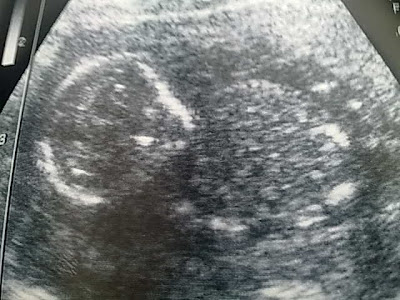

last saturday genap 4 months of my pregnancy.

so far alhamdulillah. baby in good condition. pembesaran baby normal.

| position atas ni. actually baby tgh position duduk. nampak dia dok buat streching dok pegang kaki & lutut. excercise ok!! sgt x mcm mama dia. LOL |